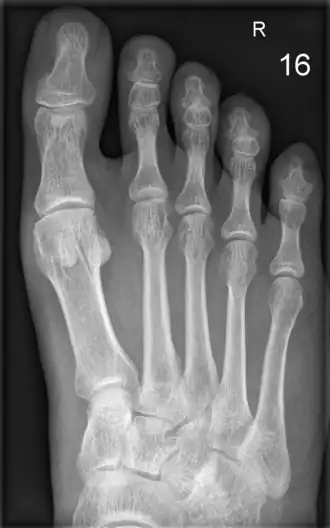

De mens heeft 14 teenkootjes in elke voet; de grote teen heeft twee teenkootjes, de andere tenen drie.

In de medische terminologie[1] wordt de Latijnse naam gebruikt en heet zowel een teen als een vinger "digitus" (meervoud "digiti"), vaak afgekort tot "digit". Beginnend bij de grote teen worden ze genummerd: digit 1, digit 2 enzovoorts t/m digit 5 voor de kleine teen. In de schrijftaal worden soms de Romeinse cijfers gebruikt (I, II, III, IV, V). Aleen de grote teen heeft een aparte naam: "Hallux". Meestal wordt er in de spreektaal gewoon aangegeven of het om de hand of voet gaat en aan welke zijde bijvoorbeeld: digit 2 van de rechtervoet. Ook in de Latijnse benaming gebeurt dit: "digit II pedes". Voor 'digits' van de hand wordt het achtervoegsel "manem" gebruikt. Om de zijde aan te geven gebruikt men "dextra" voor rechts en "sinistra" voor links. De volledige benaming van de linkerteen is dus "digit V pedes sinistra".